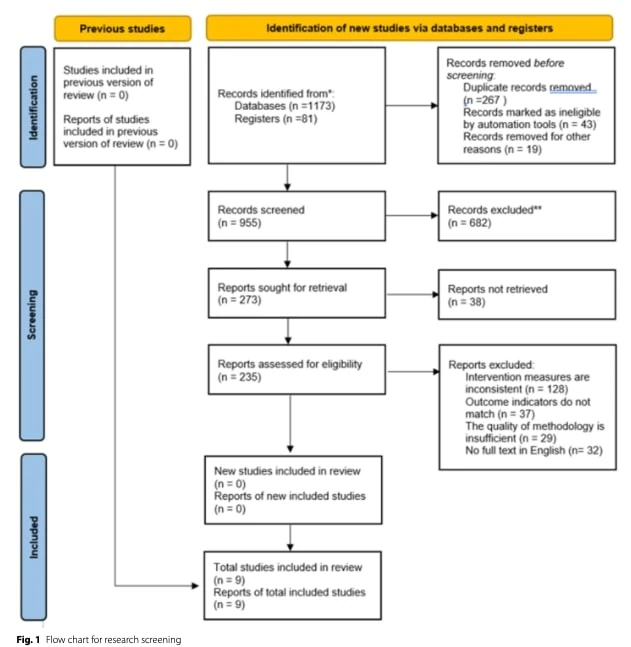

我们在 PEDro、Web of Science、Embase、PubMed 和 Cochrane 图书馆中进行了全面的文献检索,检索时间从数据库建立之初到 2025 年 6 月 1 日。 检索策略结合了与膝关节骨关节炎(膝骨关节炎)和治疗干预相关的术语,包括运动疗法、物理治疗、康复、力量训练、运动疗法和饮食干预,同时使用受控词汇和适应每个数据库的自由文本术语。

两名独立审稿人首先筛查标题和摘要,然后根据预先确定的纳入和排除标准对符合条件的研究进行全文评估。 意见分歧通过达成共识或咨询第三位审稿人来解决。 筛选过程遵循 PRISMA 2020 指南。

符合条件的研究均为随机对照试验,参与者均被诊断患有膝关节骨关节炎。 根据美国风湿病学会的标准,对运动、物理治疗、饮食疗法或患者教育等非药物干预措施进行评估。 非英语、非人类、无法查阅全文、侧重于药物治疗或使用不可靠结果测量指标的研究均被排除在外。

据报道,研究筛选过程遵循了 PRISMA 指南,该指南通常可提高文献识别和筛查的透明度、有效性和可重复性。 限制纳入随机对照试验(RCT)可能会提高证据的整体水平;但仅有RCT设计并不能保证方法的严谨性。 没有明确报告对研究质量、偏倚风险或对照研究条件的充分性进行详细评估或说明,因此有可能纳入了设计不佳的 RCT。

尽管使用了 PRISMA 流程图,但纳入研究的数量和筛选过程仍不清楚。 流程图中总共报告了九项研究被纳入综述,但同时却显示 "新纳入研究 "为零,而上一版综述中纳入的研究为零。 这种明显的矛盾可能反映了一个报告问题,而不是实际的方法错误;然而,它给读者造成了困惑。 虽然对逐步识别、筛查和资格评估进行了描述,但最后的纳入阶段对纳入研究的来源和分类缺乏明确性,影响了透明度。